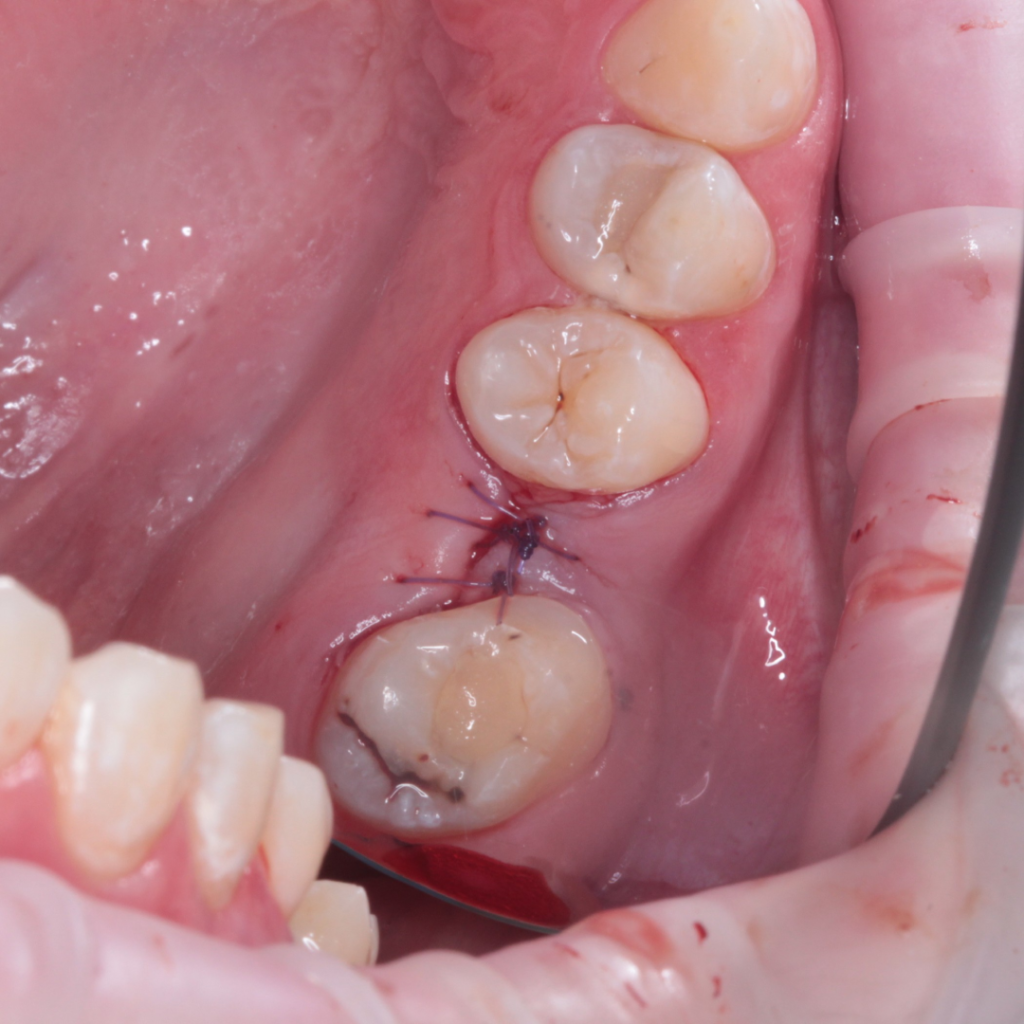

- Поднятие дна верхнечелюстной пазухи

- Установка имплантата AnyRidge

- Забор крови и центрифугирование фибриновых сгустков PRF

- Укладка фибриновых сгустков APRF под слизистую оболочку верхнечелюстной пазухи

- Наложение швов